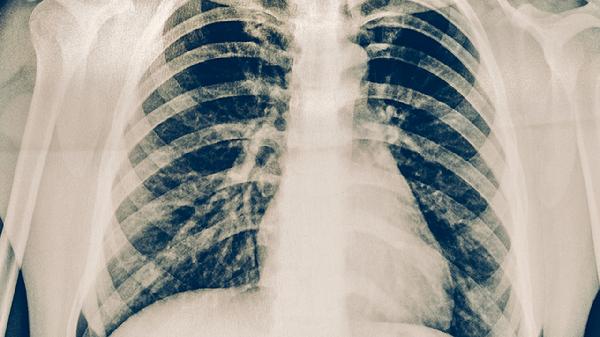

经3-6个月规范治疗后,当胸部影像显示病灶钙化、痰菌检测转阴、无发热盗汗等症状时,患者可进入恢复期锻炼。初始阶段建议从散步开始,运动时心率控制在最大心率的50%-60%,时间不超过20分钟。待体力逐步恢复后,可尝试间歇性慢跑,采用跑1分钟走1分钟的循环模式,总时长控制在30分钟内。运动过程中出现胸闷气促需立即停止,所有锻炼计划应在呼吸科医生定期评估下调整,并持续监测血沉和C反应蛋白水平。同时需注意运动环境选择空气流通场所,避免寒冷刺激诱发咳嗽。